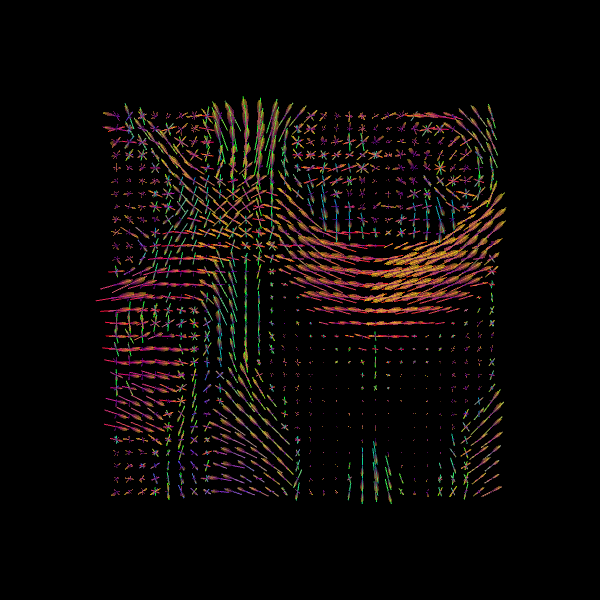

For quality assurance, we can visualize an axial slice from the direction field estimated by the CSA model. Each glyph represents a local fiber orientation derived from the ODF peaks. The underlying ODFs are not shown here.

scene = window.Scene()

scene.add(

actor.peak_slicer(

csa_peaks.peak_dirs[20:50, 55:85, 37:38], peaks_values=csa_peaks.peak_values[20:50, 55:85, 37:38], colors=None

)

window.record(scene=scene, out_path="csa_direction_field.png", size=(600, 600))

Image("csa_direction_field.png")